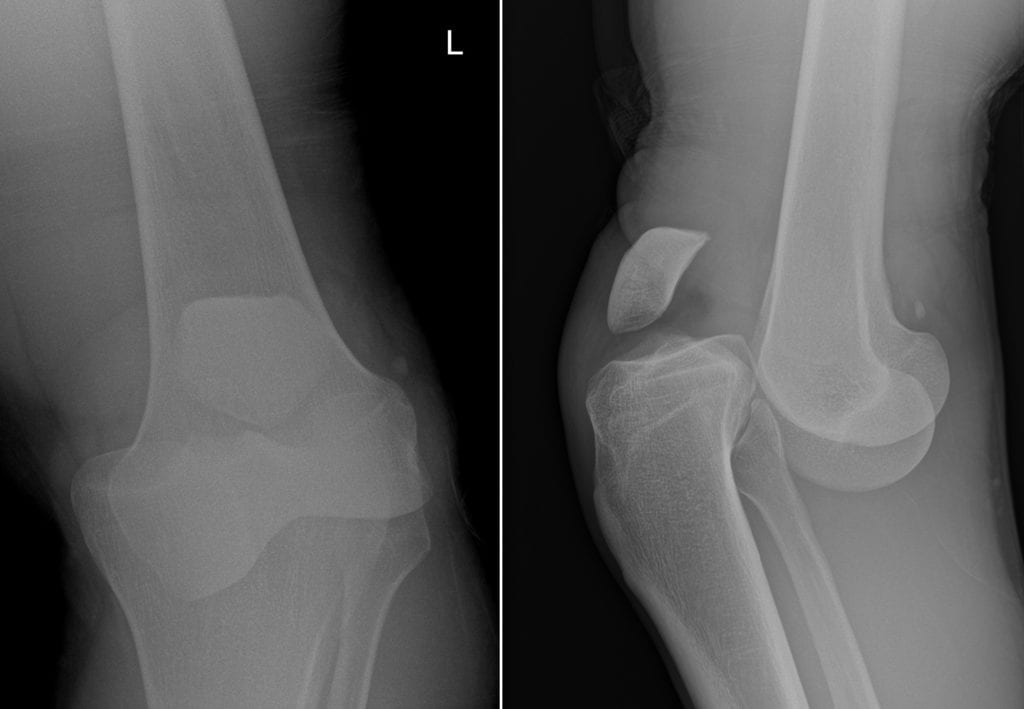

На полученных рентгенографических изображениях хондромные тела визуализируются в виде множественных шаровидных или овальных теней с четкими очертаниями. Но это исследование информативно только при наличии включений с обызвествленными участками.

Если внутрисуставные тела не содержат соли кальция, то для их обнаружения требуется проведение УЗИ, МРТ, компьютерной томографии. Эти исследования позволяют определить присутствие посторонних включений, их форму, размеры, количество.

Артроскопия и биопсия синовиальной мембраны — самые информативные диагностические мероприятия. Они помогают оценить состояние суставных структур, степень деструкции синовиальной оболочки, обнаружить хондромные тела.